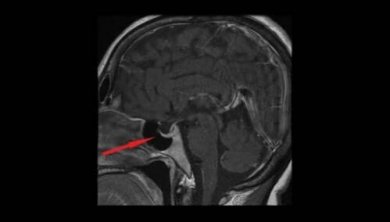

Diagnóstico do adenoma hipofisário

Primeiramente, para o diagnóstico é necessário realizar um exame físico, no qual é analisado qualquer problema de visão dupla e campo visual. Além disso, também são estudadas a perda da visão lateral ou periférica, e a capacidade de ver em certas áreas.

Assim, é realizada uma análise da função endócrina para procurar por quaisquer sinais de excesso ou irregularidade hormonal. Os parâmetros são medidos como níveis elevados de cortisol, síndrome de Cushing, ou excesso de hormônio de crescimento.

Por outro lado, os exames mais relevantes que ajudam a confirmar o diagnóstico são o de campo visual e a tomografia computadorizada (TC) e cerebral (RNM).

- Cirurgia do adenoma hipofisário: a remoção da maioria desses tumores é através da cavidade nasal. No entanto, em outros casos, é necessária uma craniotomia ou abertura do crânio.

A cirurgia nasal endoscópica consiste na introdução através das fossas nasais de um endoscópio, que desliza entre o corneto médio e o septo nasal, até que o orifício esfenoidal esteja localizado. Este orifício é aumentado para obter uma abertura suficiente do seio esfenoidal, e visualizar o solo da sela turca para extrair o tumor.